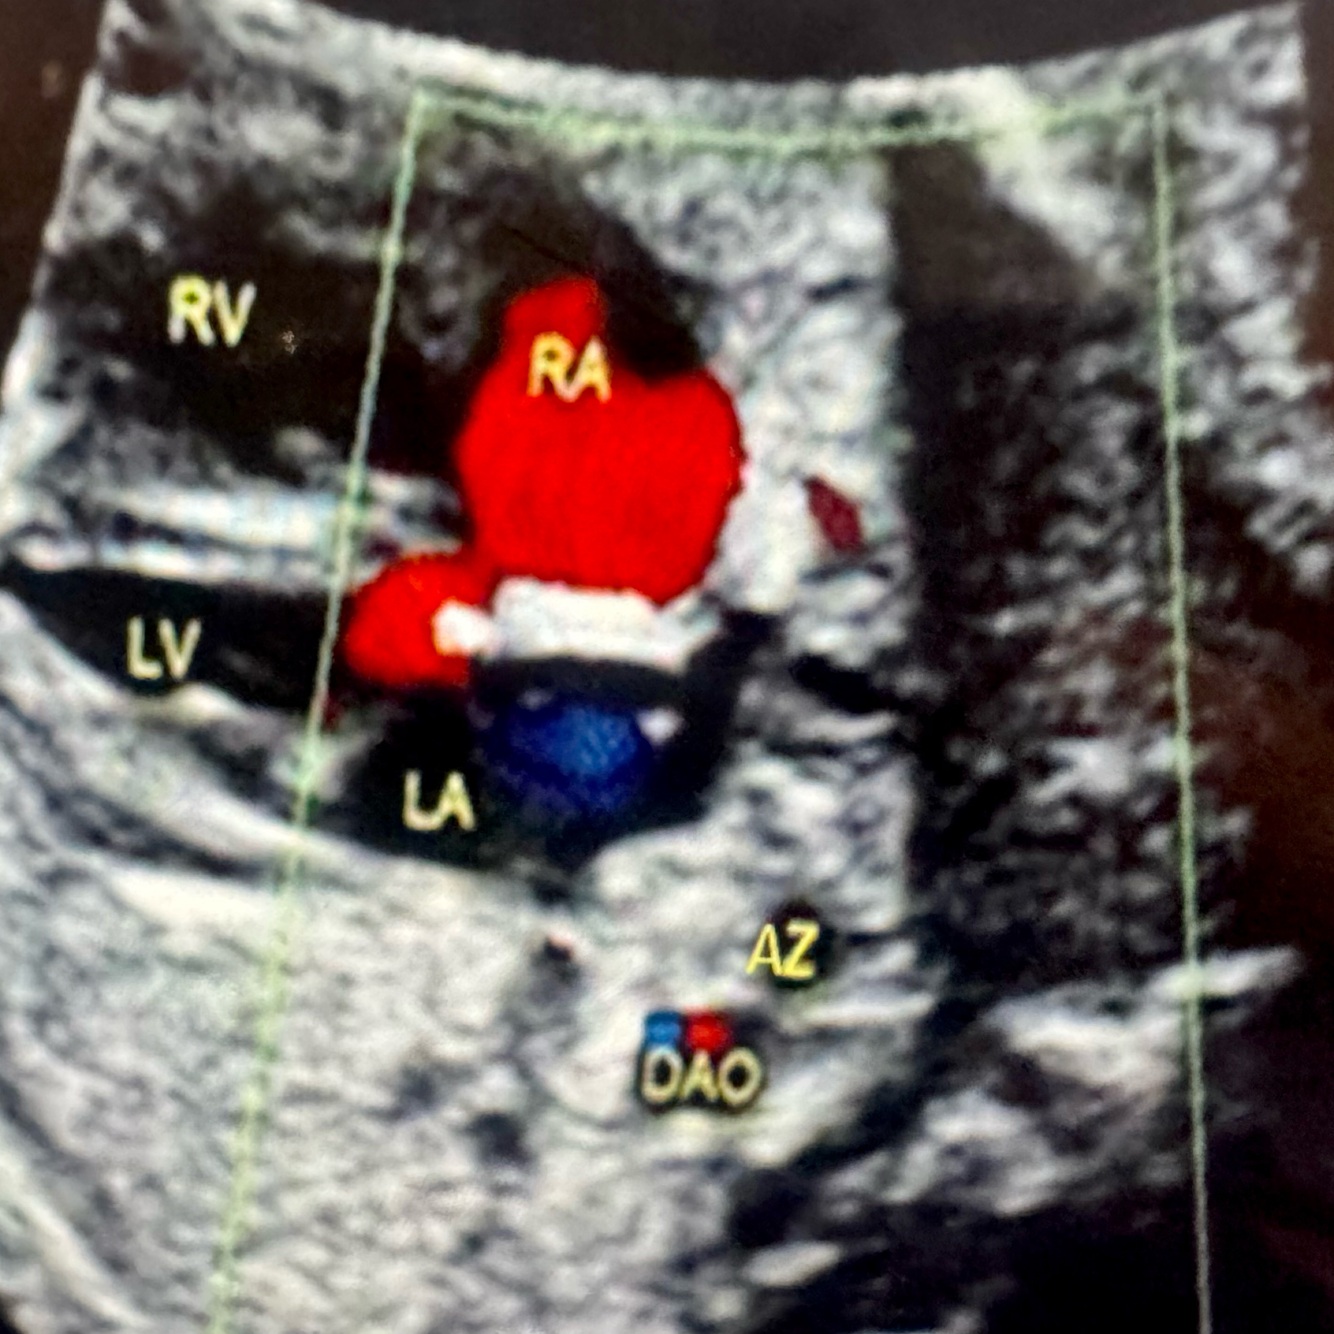

10

What pathology?

Interrupted IVC with azygos continuation (see double vessel sign)